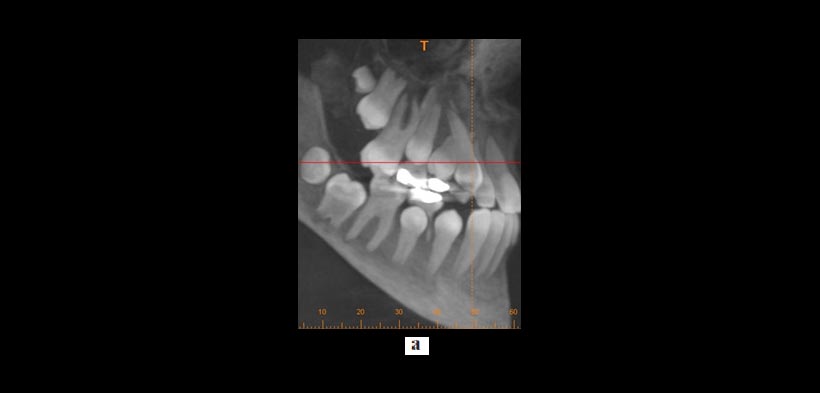

Figura 2. Uso de la CBCT en el diagnóstico y la planificación del tratamiento de los dientes transpuestos. Un caso que demuestra raíces transpuestas de los caninos superiores y los primeros premolares en la que la CBCT revela que la raíz canina está a vestibular de la raíz premolar. (a) Reconstrucción tridimensional y (b, c) imágenes transversales y la ubicación de la raíz. Todos estos cortes tomográficos pueden ayudar al clínico a optimizar la planificación del tratamiento.